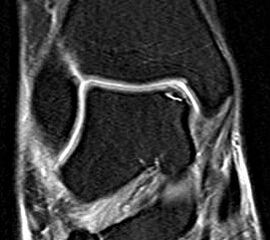

Abbildung 13-14, Video 7

Osteochondrale Läsion an der rechten medialen Talusschulter. Die Knorpelfläche erscheint bei der initialen Inspektion häufig intakt, erweist sich dann bei der Tasthakenpalpation allerdings als deutlich weicher verglichen mit dem umliegenden intakten Knorpelgewebe. In den meisten Fällen lässt sich mit dem Tasthaken ein Riss in der Oberfläche nachweisen und eine lose chondrale bzw. osteochondrale Schuppe abheben. Die instabilen Knorpelanteile und die sklerotisch veränderten Anteile der subchondralen Knochenschicht müssen mit einer Kürette oder einem Shaver entfernt werden, bis ein stabiler Rand aus gesundem Knorpelgewebe besteht. Die Eröffnung des subchondralen Knochens erfolgt mit einer gebogenen Ahle. Anschließend (ggf. nach dem Öffnen der Blutsperre) sollten kleine Blutungen aus den Knochenkanälen erkennbar sein.